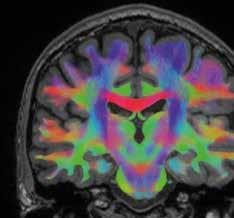

De onderzoekers brengen daarvoor bepaalde verbindingen of wittestofbanen in de hersenen in beeld. ‘We onderzoeken de

hersenplasticiteit, met name de verbindingen tussen de hersencellen die te maken hebben met het evenwicht,’ legt doctoraatsonderzoeker Angelique Van Ombergen uit. Die wittestofbanen worden in beeld gebracht door middel van Diffusion Tensor Imaging (DTI) een revolutionaire techniek die de dienst radiologie van het UZA, onder leiding van prof. dr. Paul Parizel, sinds enkele jaren beheerst. Ook het Visielab van de Universiteit Antwerpen laat zijn geavanceerde technieken los op de beelden.